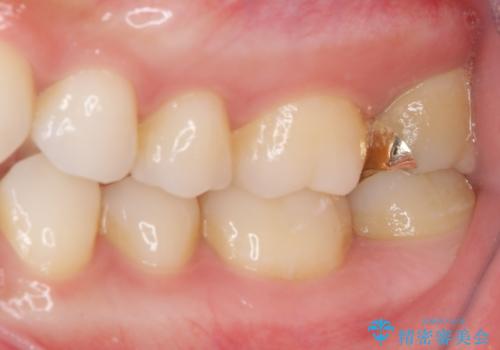

- 奥歯にフロスが引っかかるようになり、虫歯ではないかとのことで来院された患者様です。

レントゲン写真より、1番奥の歯に虫歯があることが分かりました。

奥で目立たないことから、虫歯の再発リスクが最も低く、咬合力による歯への負担も少ないゴールドインレー(PGAインレー、白金加金インレー)にて修復治療をすることとしました。